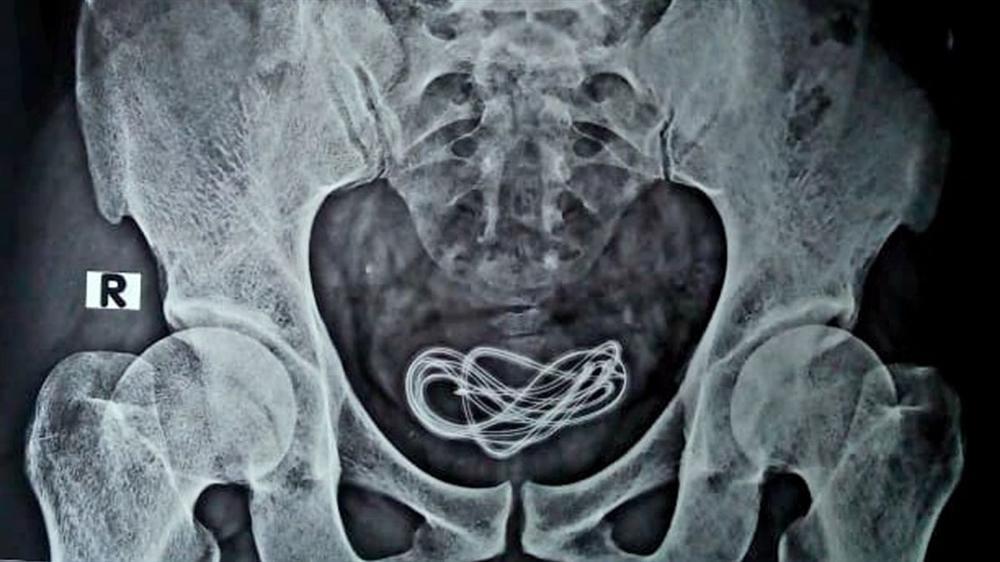

Ảnh chụp X-quang cho thấy một sợi dây sạc dài hai feet nằm trong bàng quang, tuy nhiên nó được đưa vào qua đường niệu đạo, theo ống dẫn từ dương vật đến bàng quang chứ không phải từ đường miệng nuốt vào như lời bệnh nhân khai.

Hình ảnh chụp X-quang cho thấy sợi dây sạc nằm trong bàng quang của bệnh nhân chứ không phải trong dạ dày